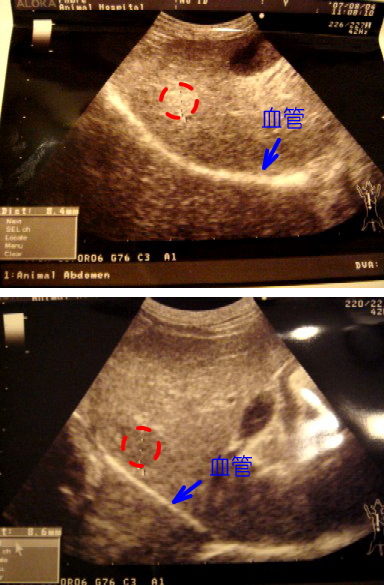

今日はね、初めての病院でチックンしてもらったの 門真のお目目の先生に教えてもらった病院なの 母さんは、今までの検査結果を全部入力して持って行ったんだよ 心配性だよね 母さんの心配をよそに、ボクは今日もクレクレ攻撃で叱られたの〜 マンションから8kmほどの場所にあるK動物病院 事前に門真の病院から聞いてと、電話してありました マックが今受けている治療の全てを持って行きました いつか走らなくてはいけないのか それとも症状が落ち着いて、京都での治療になるのか どういう形でお世話になるかは分りませんが 担当して下さった先生は、私の話をよく聞いて下さいました 門真のN先生のこともご存知で、何かあっても連絡を取り合ってもらえるかも・・・ そう思い少し安心しました 「今後こちらで治療をと、考えればいいですか?」と問われた時 言葉に詰まりました 私自身の切り替えがまだ出来ていないことに気がついたのです 昨年の9月から積み上げた先生への信頼は 自分で思っていた以上でした 時間さえあれば、マックが元気なうちは通いたい いつもこの時間とのジレンマです 8/4の肝臓エコー 参考の為にデジカメで撮っておきました ![]() |

今日もマックとふたり旅 私が運転して、マックが助手席のキャリーに このパターンは、マックにとってベストかもしれません 殆ど泣く事もなく、落ち着いて寝てくれていました 小春は、母と姉が交代で付いていてくれました (皆に支えられてできている治療ですね) 誰ががいると安心して、よく寝ているようですが、大丈夫そうなので帰ろうとすると 「ヒィ〜ヒィ〜」っと泣いて引きとめ、結局私が帰った2時過ぎまで居てもらうことになりました マックがいれば、お留守番も平気なんだけど いつかひとりになる小春・・・どうなるのか・・・ 今日はいつも通りの血液検査とエコー やはりカルシウム値が上昇 この結果で疑われる症状「上皮小体機能亢進症」の検査を追加してもらいました これが最後の検査 もちろん、定期的な肝臓・腎臓・エコーの検査は続けていかなければなりませんが 原因を突き止める検査の、考えうる全てです 肝臓の数字は良くなってきました 久々の1000台です(^^v) 先生「肝臓だけを見ると、すごく良い感じになってきたのに、ボクはもうこれを消したいです」と 検査表のカルシウム値を手で隠されました 腎臓、高カルシウム血症もやっかいです このまま進むと点滴による緩和しかないそうです 先生も苦悩されていました クッシング・・・ このひとつの病気がこんなにもバランスを崩してしまうのか 改めて、この病気の難しさを知った気がしました